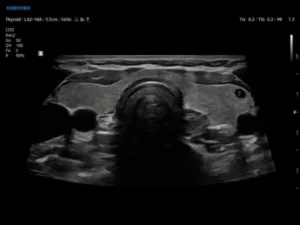

В-режим

Подавляющее большинство сканирований производится на аппаратуре, функционирующей в двумерном В-режиме (Brightness Mode, «brightness» – яркость), который в режиме реального времени отображает анатомические структуры.

Изображение при В-сканировании формируется в результате неодинакового проведения ультразвуковых сигналов через различные органы. Если ультразвук беспрепятственно проходит сквозь образование, не отражаясь от него, на дисплее это место будет выглядеть черным («эхопрозрачным»). Если структура умеренно поглощает эховолны и частично их отражает, она будет иметь среднюю эхогенность и отображаться в оттенках серого. Если объект полностью отражает ультразвуковые сигналы, то на мониторе будет визуализироваться только его граница в виде гиперэхогенной линии белого цвета. Осмотреть более глубокие структуры невозможно.

Современные ультразвуковые аппараты могут регистрировать до 1024 градаций серого цвета, благодаря чему можно разграничить анатомические структуры, даже незначительно отличающиеся друг от друга по акустическому сопротивлению.

13.jpg

Рис.1. Щитовидная железа, В-режим.